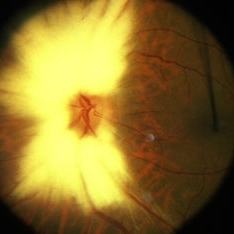

Myelinated Nerve Fiber Layer

Myelinated Nerve Fiber Layer

Jan 30 2015 by H. Michael Lambert, MD

Myelin of optic nerve head covering optic nerve grossly.

Condition/keywords: myelinated nerve fiber layer